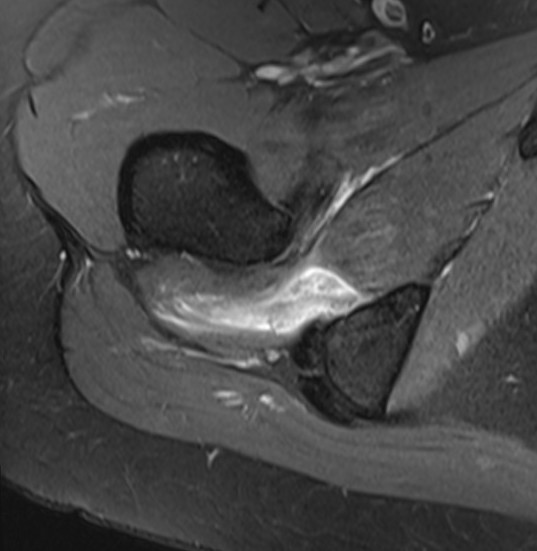

MRI

Reduced ischiofemoral space - distance between the lesser trochanter and the ischial tuberosity

Reduced quadratus femoris space - distance between hamstring tendon and iliopsoas

Inflammation / edema in quadratus femoris +/- fatty degeneration